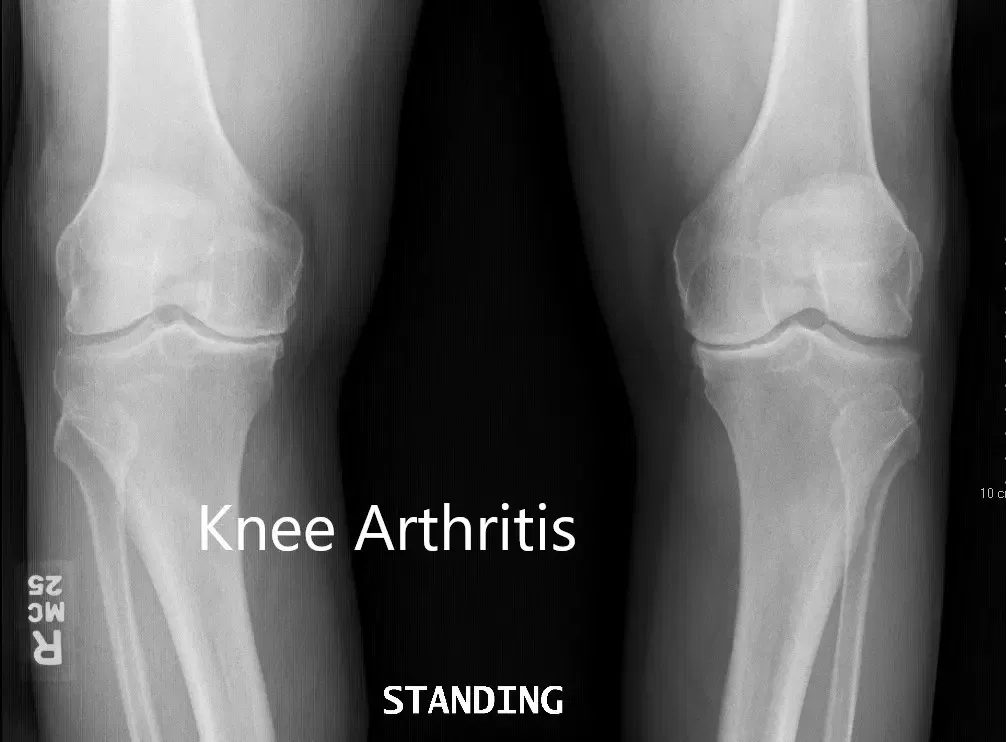

Her imaging studies of both the knee revealed severe tricompartmental osteoarthritis. Considering her lifestyle limiting knee pain, she was advised bilateral custom total knee replacement. Risks, benefits, and alternatives were discussed with the patient at length. She agreed to go ahead with a bilateral custom knee replacement.

Preoperative X-ray showing the AP view of both knees.